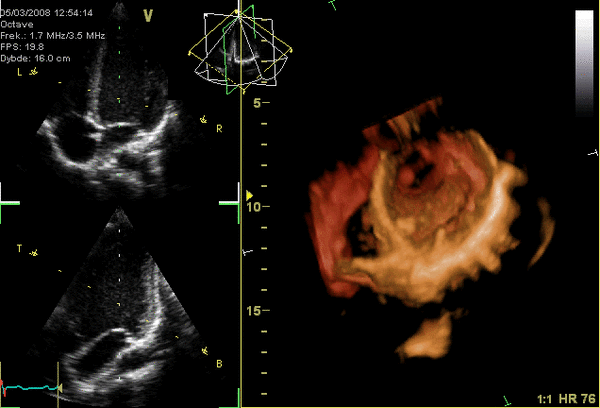

Эхокардиография (ЭхоКГ) — это ультразвуковая диагностика заболеваний сердца. В этом исследовании оцениваются размеры сердца и его отдельных структур (желудочки, предсердия, межжелудочковая перегородка, толщина миокарда желудочков, предсердий и т. д.), наличие и объём жидкости в полости перикарда, состояние клапанов сердца, а также, в допплеровском режиме, кровоток в сердце и магистральных сосудах. С помощью специальных расчетов и измерений эхокардиография позволяет определять массу миокарда, сократительную способность сердца (фракцию выброса, сердечный выброс и др.). Обычно ЭхоКГ проводится через грудную клетку (трансторакально), также существует чреспищеводная ЭхоКГ (ЧП-ЭхоКГ), когда специальный эндоскопический датчик помещается в пищевод. ЧП-ЭхоКГ позволяет лучше рассмотреть сердце, так как датчик располагается к сердцу ближе, чем при обычной ЭхоКГ и поэтому становится возможным использовать датчик с более высокой частотой ультразвука, что повышает разрешающую способность изображения. Также существуют специальные высокочастотные интраоперационные датчики, которые помогают во время операций на сердце.

4D-ЭхоКГ представленная на изображении, позволяет получать живое 3D-изображение сердца, то есть в реальном времени, что может быть также полезно, для проведения данной методики требуется специальный 4D-датчик.